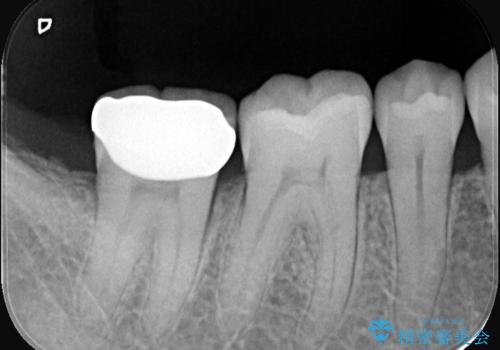

- お口の中にある銀歯を全てなくして、白く健康的な状態にしたい」という主訴でご来院されました。長年使用してきた複数の銀歯は、経年劣化により適合が悪くなっており、一部では内部で二次カリエス(虫歯の再発)も認められました。

患者様と相談の上、全ての金属(メタル)を取り除き、生体親和性が高く審美性に優れた素材へ置き換えるメタルフリー治療の計画を立案。部位や欠損の大きさに合わせ、セラミックインレーおよびセラミッククラウンを用いて、お口全体の調和を整えることとしました。

銀歯の除去と精密な再治療: 古い銀歯を一つひとつ丁寧に取り外し、内部の虫歯を徹底的に除去。神経を保護するための処置を行った上で、適合性を極限まで高めるために精密な型取りを行いました。

オールセラミックによる修復: 天然歯のような光の透過性と硬さを持つオールセラミックを使用しました。奥歯であっても、患者様固有の歯の色調や咬み合わせの溝を忠実に再現した修復物を装着。金属を一切使用しないことで、金属アレルギーのリスクを排除し、歯肉の色が黒ずむ心配もなくなりました。